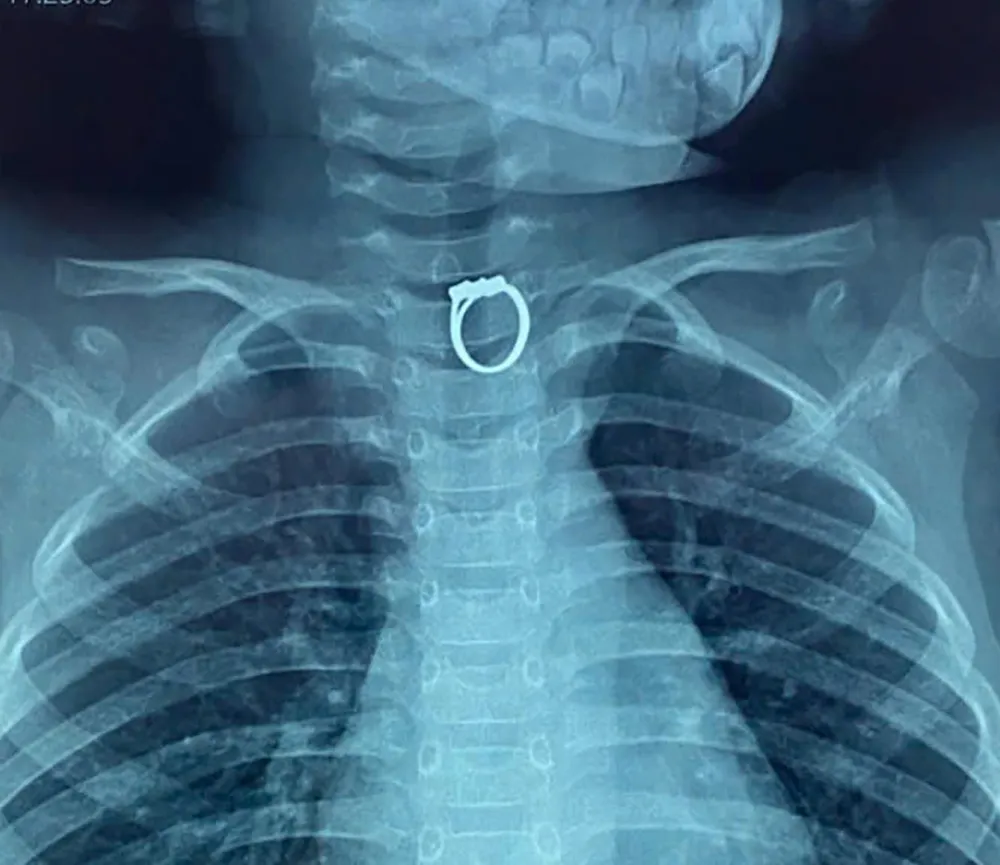

এক্স-রে-এর মাধ্যমে, ডাক্তাররা শিশুটির খাদ্যনালীতে একটি বিদেশী বস্তু, একটি আংটি খুঁজে পান, তাই তারা শিশুটিকে অস্ত্রোপচার কক্ষে স্থানান্তরিত করেন এবং একটি এন্ডোস্কোপি করেন। ফলস্বরূপ, ডাক্তার খাদ্যনালী থেকে ধাতব আংটিটি অপসারণ করেন এবং শিশুটির স্বাস্থ্য স্থিতিশীল হয়।